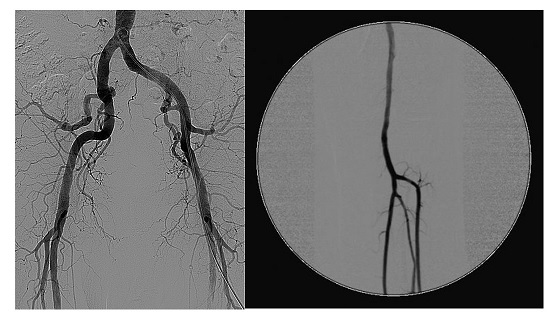

Il dibattito ha messo in luce i benefici dell’anidride carbonica come mezzo di contrasto, soprattutto per i pazienti con insufficienza renale o a rischio di reazioni avverse allo iodio. Un collegamento in diretta dal Policlinico S. Orsola di Bologna ha mostrato l’utilizzo della CO₂ su un paziente con aneurisma dell’aorta addominale, illustrato dal professor Enrico Gallitto.

Molti i contributi dal mondo clinico e istituzionale. Stefano De Lillo, vicepresidente dell’Ordine dei Medici di Roma: «La CO₂ offre nuove opportunità diagnostiche per garantire più sicurezza ai pazienti fragili. È fondamentale diffondere conoscenza tra i professionisti sanitari». Mauro Gargiulo, direttore di Chirurgia Vascolare al S. Orsola di Bologna: «L’uso della CO₂ ha rivoluzionato l’approccio endovascolare, permettendo oggi procedure con quantità minime di iodio o addirittura a zero-contrast, senza compromettere la qualità delle immagini». Anna Lisa Mandorino, segretaria generale di Cittadinanzattiva: «È un esempio concreto di medicina personalizzata che riduce le complicanze e migliora la sicurezza dei pazienti più a rischio»Angela Deni, Confindustria Dispositivi Medici: «L’innovazione deve entrare nel sistema sanitario senza ostacoli. Servono codifiche aggiornate, tariffe adeguate e formazione continua per il personale». Sebastiano Zannoli, presidente di Angiodroid S.p.A.: «Serve un ecosistema condiviso tra istituzioni, clinici e industria per rendere l’innovazione accessibile, riducendo costi e migliorando l’efficienza del sistema sanitario».